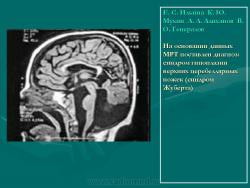

На основании данных МРТ поставлен диагноз: синдром гипоплазии верхних церебеллярных ножек (синдром Жуберта).